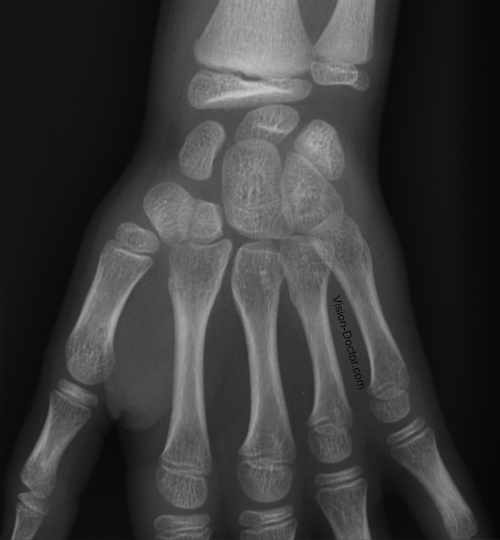

Röntgen (X-Ray)